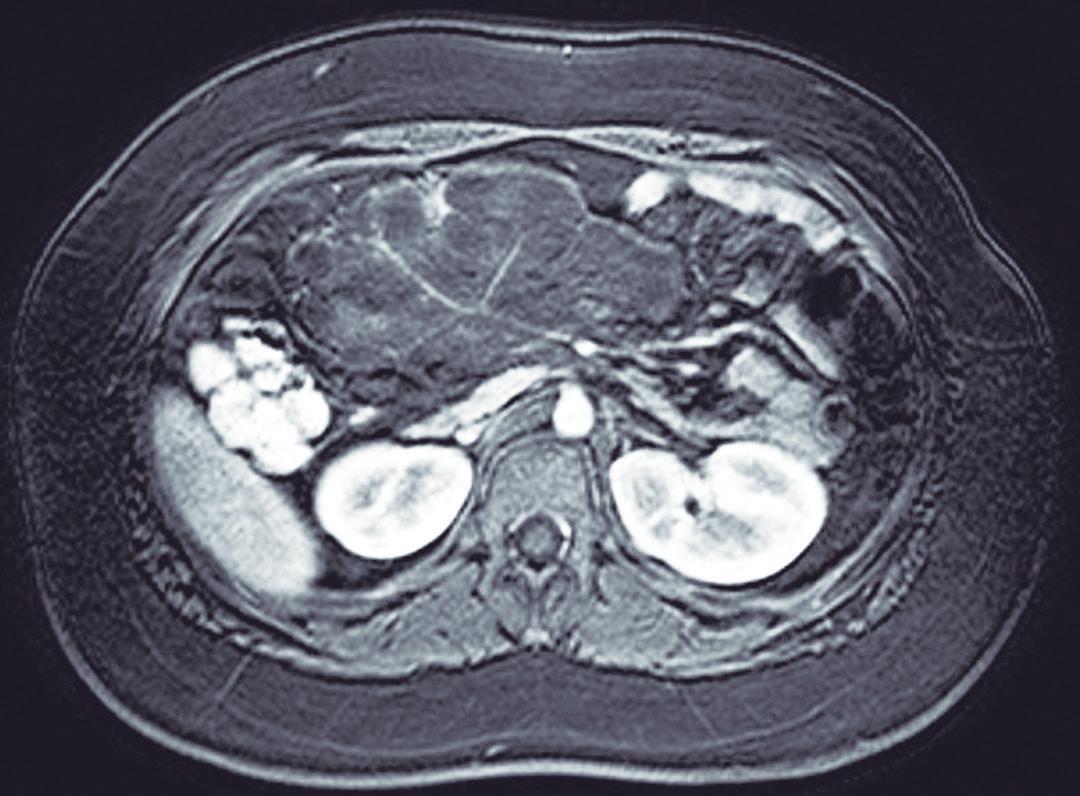

La endoscopía superior es un procedimiento fundamental para el diagnóstico, la evaluación de la respuesta al tratamiento y el monitoreo a largo plazo de la actividad de la EEo. Los hallazgos endoscópicos típicos incluyen edema (reducción de vascularidad), anillos esofágicos fijos, exudados blancos, surcos longitudinales, estenosis, estrechamiento de la luz esofágica, friabilidad de la mucosa (mucosa en papel crepé) y una consistencia firme de la mucosa al realizar biopsias (signo de “tracción" o "resistencia”) en pacientes con fibrosis (Figura 1). Estos hallazgos no son patognomónicos y no constituyen un criterio diagnóstico; sin embargo, cuando se evalúa de forma cuidadosa, en la gran mayoría de los casos se pueden observar.19-21

En el panel A se observa un esófago con edema difuso y pliegues longitudinales; en el panel B se aprecia edema con pliegues y exudados blanquecinos; en el panel C se evidencia un estrechamiento luminal acompañado de anillos esofágicos y exudados; y en el panel D se muestra un desgarro mucoso posterior a la dilatación con bujía de Savary, hallazgo esperado tras este procedimiento terapéutico.

Figura 1. Características endoscópicas de la esofagitis eosinofílica